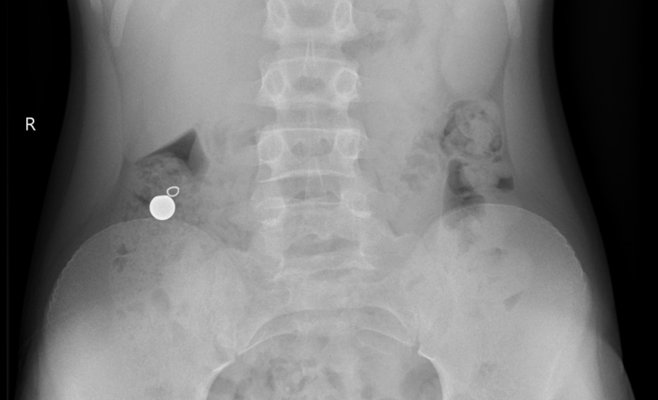

Одному из пациентов повезло — магнитные шарики вышли естественным путём, не вызвав осложнений. Однако другие дети до сих пор остаются в больнице, и двум из них требуется срочная операция. Рентгеновские снимки, опубликованные больницей, показывают, что у некоторых детей внутри тела оказалось до пяти магнитных шариков, что может привести к серьёзным повреждениям внутренних органов.